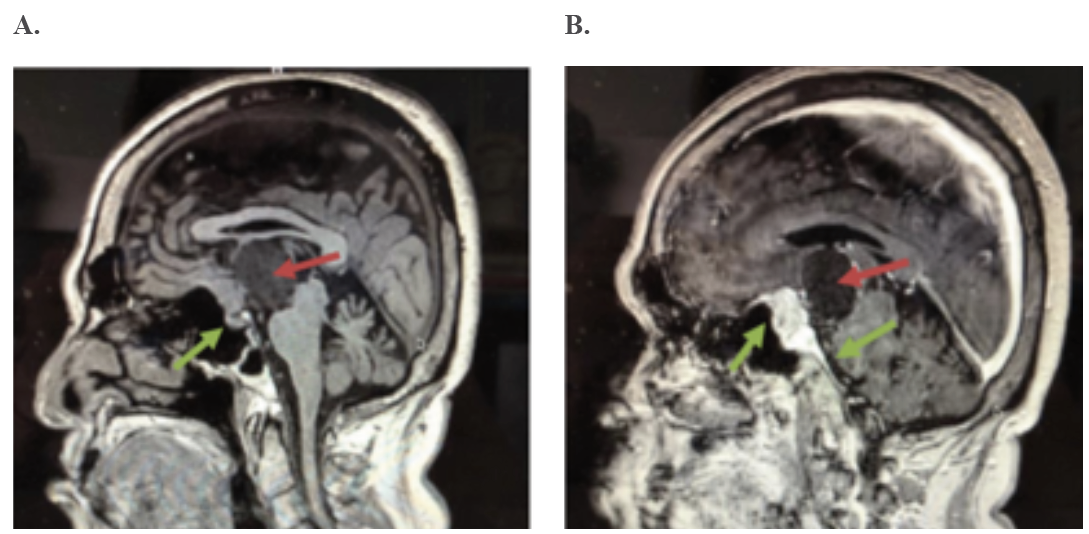

En el estudio de resonancia magnética nuclear (RMN) se evidencia una lesión ocupante de espacio (LOE) mixta, sólida y quística, supraselar con extensión intraventricular, sin hidrocefalia, compatible con un craneofaringioma y un meningioma (Ver figura 1 A y B). En el estudio se puede evidenciar como la lesión desplaza el techo del tercer ventrículo o el piso del ventrículo lateral, el cual forma parte del sistema límbico donde se encuentra parte de los circuitos de la memoria reciente, por lo que su compresión explica la pérdida de memoria reciente con la cual se presenta el paciente.

Se plantean los siguientes diagnósticos: 1. LOE mixto supraselar con extensión intraventricular compatible con craneofaringioma 2. Meningioma de la región sellar. 3. Insuficiencia adrenal (IA) secundaria o terciaria, en vista de presentar valores de glucemia en 67 mg/dL, Na 134 mmol/L, niveles de cortisol < 10 μg/dL con clínica de astenia y adinamia. El paciente no se pudo realizar la prueba de estimulación con corticotropina para confirmar el diagnóstico de insuficiencia adrenal. El diagnóstico se realizó en base a la clinica del paciente y hallazgos imagenológicos, pudiéndose plantear IA secundaria o terciaria, ya que la lesión tiene un componente supraselar y la glándula hipófisis se encuentra indemne. Se indicó reemplazo con glucocorticoides en el preoperatorio.